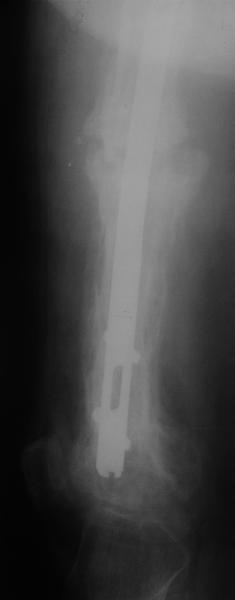

Еще один пример. Пациентка с юга России, прислала рентгенограммы через год. На сегодня прошло 2 г. 8 мес. после операции. Несмотря на не очень убедительный процесс сращения, пациентка ходит. Учитывая остеопороз при Педжете, решили, что динамизировать вообще не нужно.